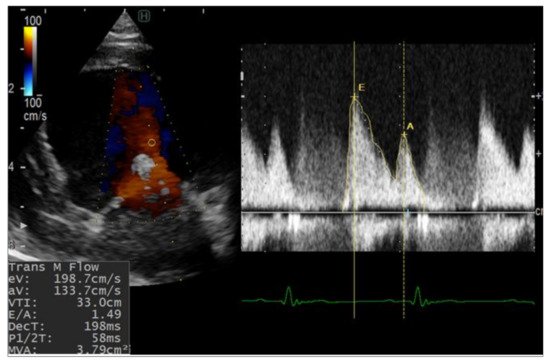

Figure 4. Representation of color M-mode echocardiography used to measure the intraventricular pressure gradients (IVPG) from left apical four-chamber view. Firstly, the mitral inflow was observed, then color M-mode echocardiography (CMME) was switched on and photos were captured for further calculation MATLAB. (A) color M-mode echocardiography; (B) three-dimensional temporal and spatial profiles of the left ventricular IVPG; (C,D) IVPG in early diastole-, the top (blue), middle (red), and bottom (blue) lines represent inertial, total, and convective IVPG, respectively.

2.2.3. Color M-Mode Echocardiography (CMME)

Intraventricular pressure gradient (IVPG) was obtained from the apical four-chamber view through CMME and analyzed with homemade software in MATLAB [17]. Details of the used procedure and method of calculation of IVPG have previously been described [11]. Total IVPG, basal IVPG, and mid-to-apical IVPG were reported.

Table 2 summarizes the 2D-STE (Figure 3) and CMME (Figure 4) data in the two operated dogs. The radial strain was increased in both dogs during the observation period. The total and basal IVPGs were only increased in the first dog at week 1 postoperative, then they reduced; meanwhile; in the second dog, the total and basal IVPGs remained higher than the baseline until week 4 post-operative. The mid-to-apical IVPGs were found to be elevated in the dog 1 until week 4 compared with the baseline; however, it was reduced in dog 2.

The correlation between E/e’ and the pulmonary capillary wedge pressure can be challenging in patients with altered MV geometry. IVPG is the force that suctions the blood from the left atrium into the left ventricle during early diastole. The basal part of IVPG has been shown to correlate with left atrium pressure, and mid-to-apical IVPG has been correlated with myocardium movement [35]. In dog 1, the hemodynamic parameters changed dramatically, with peak E-wave value at 2 weeks postoperation nearly four-fold higher than that measured at the baseline, which indicated elevated left atrium pressure caused by mitral stenosis. The pulmonary edema observed at 2 weeks postoperation in dog 1 was also confirmed to be due to hemodynamic changes. In dog 2, pulmonary edema was not observed, despite a high E/e’ ratio. For the evaluation of congestion after TEER implantation, basal IVPG appears to be a more reliable measure than E/e’.